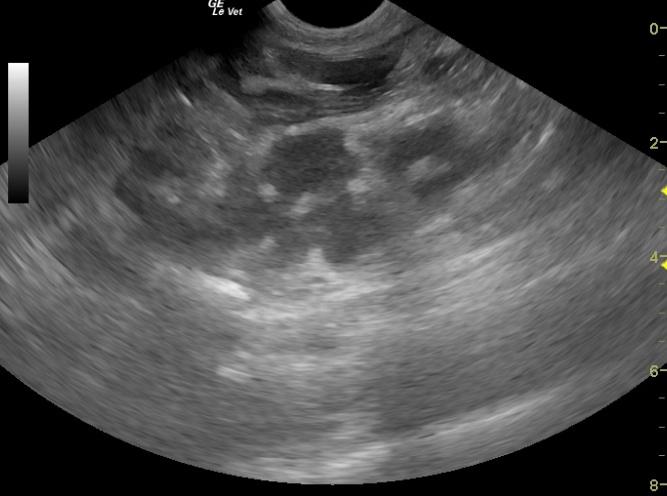

A 12-year-old MN DSH cat was presented for acting hungry but not eating, polyuria, and progressive weight loss. The only significant abnormality on physical examination was a thickened intestine.